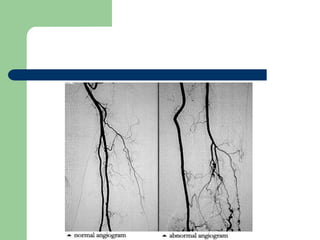

   Görüntüleme yöntemi: duplex USG, MR

, BT, anjiografi

    Arteriografi destekleyicidir